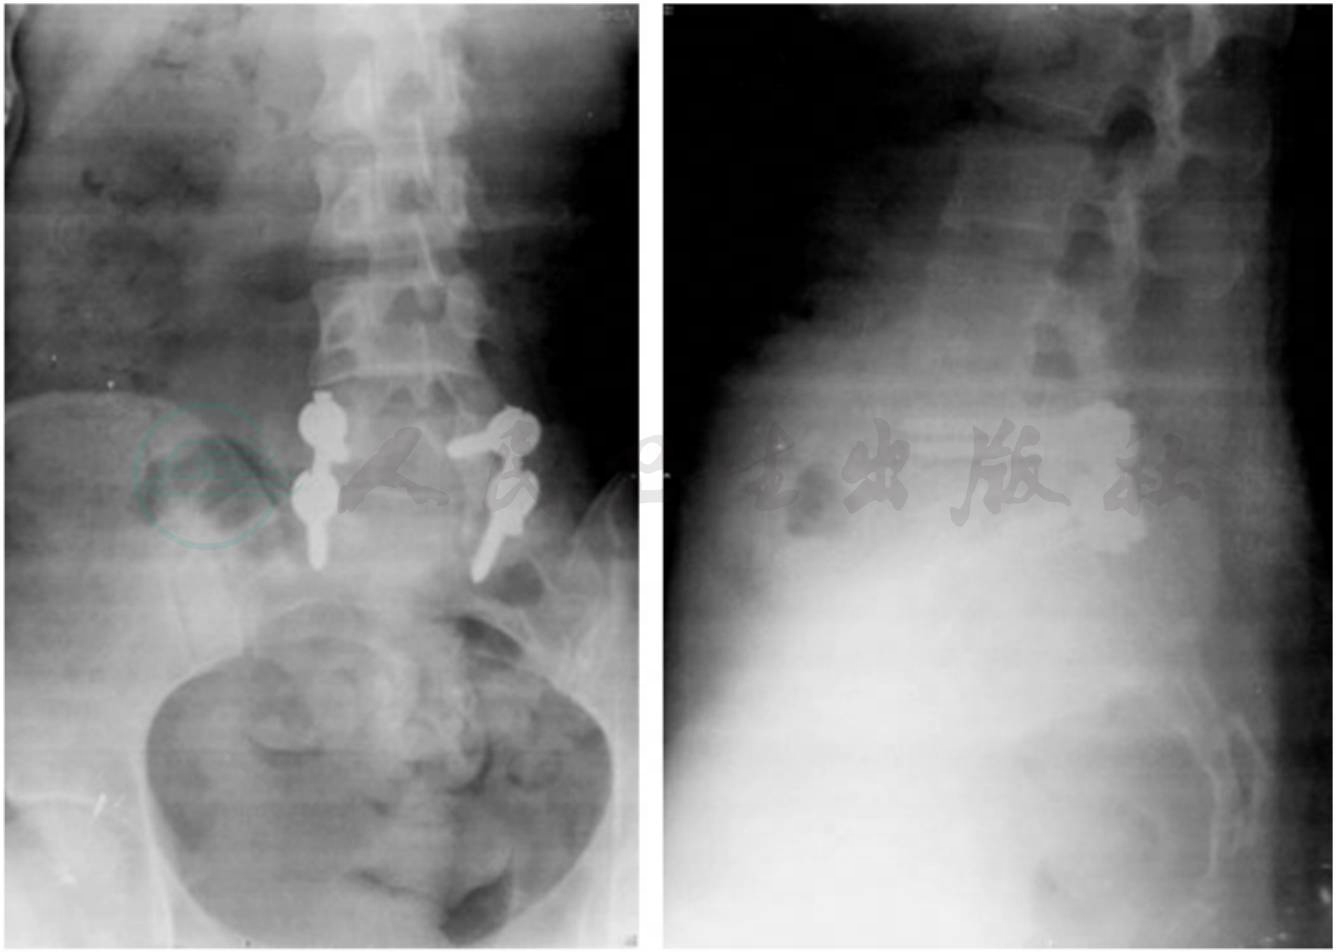

本例患者手术后,马鞍区症状与体征基本消失。手术后转血液科进一步化疗与放疗。术后腰椎X线片,见图2。

图2 全椎板减压,内固定